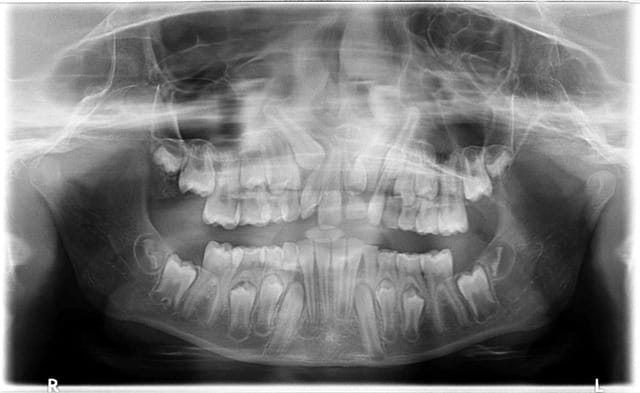

Besoin d'avis sur la prise en charge pour cette petite fille de 10 ans .

Sa 61 est toujours présente, rhisalysée. C'est au dessus que ça bloque, à la radio on peut voir une sorte de mésiodens qui bloquerai la 21.

Vos avis ? Stomato puis ortho ou l'inverse ?

à 10 ans, 21 pas en place, c'est sûr, il faut déjà opérer retirer 61 et le mesiodens, l'ortho pourra être consulté dans la foulée car il y a un encombrement important dans le secteur antérieur

Une 3D pour faire un diagnostic précis... et de longues explications pour les parents... tout cela avant d'extraire cette 61....

Plus que le mesiodense c'est le rapport des canines avec les latérale qui m’inquiète

ça change beaucoup pour le chirurgien qui va l'enlever!!!

Mais la 3D va nous permettre de préciser le rapport anatomique avec les dents définitives, la position des canines et donc le ou les plans de traitement possible.

oui, ce qui est intéressant ce sont les rapports des 13 et 23 avec les apex des 12 et 22 qui pour l'instant semblent encore intact.